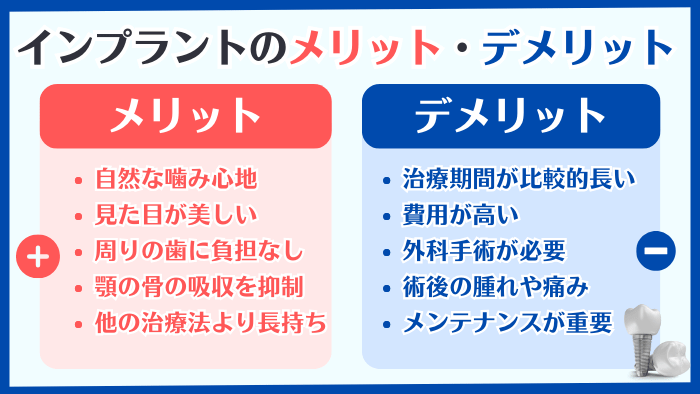

2:インプラントのメリットとデメリットを正しく理解しよう

「絶対ダメ」という否定的な意見だけではなく、インプラントを肯定する意見も多数あります。

つまり、

- メリット

- デメリット・リスク

その両方をしっかりと理解することが、あなたにとってベストな治療法を選択するために大切なポイントなのです。

2-1:インプラントのメリット

インプラントのメリットは、大きく分けて以下の5つです。

- 天然の歯と変わらない噛み心地

→自分の歯のようにしっかりと噛めるため、食事の制限がほとんどありません。 - 見た目が自然で美しい

→周りの歯と調和し、美しい口元を取り戻すことができます。 - 周りの歯に負担をかけない

→ブリッジのように健康な歯を削る必要がありません。

→部分入れ歯のように、金具をかけることで周囲の歯にダメージを及ぼすこともありません。 - 顎の骨の吸収を抑制する

→インプラントは顎の骨に直接埋め込まれるため、骨の萎縮を防ぎ、顎の形状を保つのに役立ちます。これにより、顔の輪郭も維持されます - 他の治療法よりも長持ちする

→適切なケアを行えば、インプラントは長期間使用でき、場合によっては半永久的に使えます。

2-2:インプラントのデメリット・リスク

一方で、インプラントのデメリット・リスクは以下の5つです。

- 治療期間が比較的長い

→手術から被せ物の装着まで、数ヶ月の期間を要することがあります。 - 費用が高い

→インプラントは他の治療法(保険適用のブリッジや入れ歯)に比べて高額になることが多く、基本的に保険が適用されません。 - 外科手術が必要

→インプラントを埋め込むためには外科手術が必要であり、手術に伴うリスク(感染、神経損傷など)が存在します - 術後の腫れや痛み

→手術後、一時的に腫れや痛みが生じることがあります。ただし、処方された痛み止めや抗生物質をお飲みいただければ、痛みや腫れはかなり緩和されます。 - メンテナンスが重要

→インプラントは自然の歯と同様に、定期的なメンテナンスが必要です。これを怠ると、インプラント周囲炎などの問題が発生する可能性があります。

インプラント治療は、これらのメリットとデメリットの両方をよく理解・比較した上で、治療を検討することが重要です。

それでは最後に、本記事の重要なポイントを簡単におさらいしていきます。

▼インプラントのメリット

- 天然の歯と変わらない噛み心地

- 見た目が自然で美しい

- 周りの歯に負担をかけない

- 顎の骨の吸収を抑制する

- 他の治療法よりも長持ちする

▼インプラントのデメリット

- 治療期間が比較的長い

- 費用が高い

- 外科手術が必要

- 術後の腫れや痛み

- メンテナンスが重要